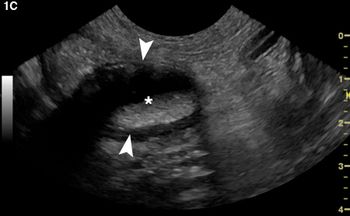

You've got ultrasound questions. We've got answers. Consider these cat-veats to maximize your machine.